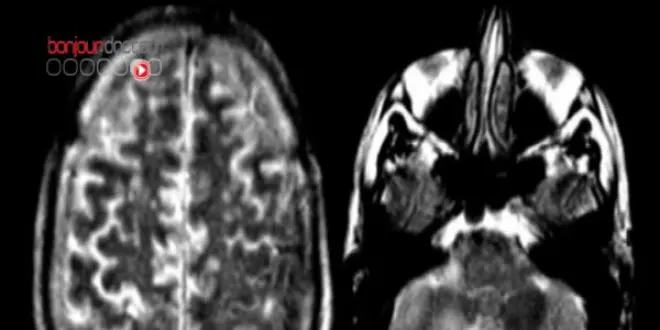

L'examen de la taille de certaines parties du cerveau pourrait aider à diagnostiquer plus tôt la maladie d'Alzheimer.

Certaines parties du cerveau sont connues pour être plus vulnérables que d'autres à la maladie d'Alzheimer.

Des chercheurs américains ont donc eu l'idée de les examiner de près à l'aide de scanners. 159 personnes, âgées en moyenne de 76 ans et indemnes de démence ou de problème de mémoire ont participé à cette étude durant trois ans. Régulièrement les chercheurs ont mesuré l'épaisseur de certaines zones du cortex cérébral, zones dont on a déjà par le passé constaté qu'en cas de maladie d'Alzheimer elles avaient tendance à rétrécir. Les patients, en fonction des mesures établies, ont été ensuite classés en trois groupes : haut risque, risque moyen et faible risque de développer la maladie.